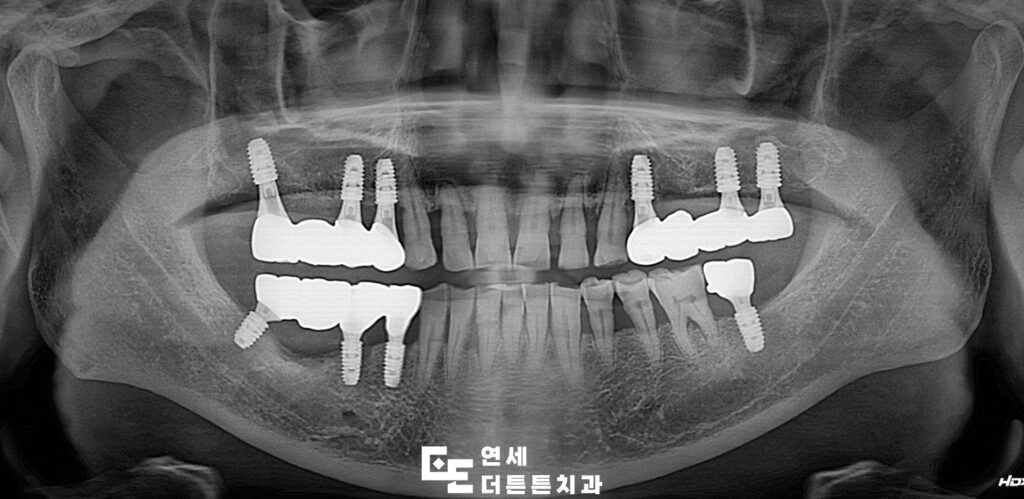

상태가 좋지 않았던 어금니를 발치한 뒤, 임플란트를 식립하고 최종 보철물까지 완성한 모습입니다.

어금니 부위는 구조적으로 강한 저작력이 가해지기 때문에 임플란트 식립 시 잇몸뼈의 양과 밀도, 보철물의 강도 및 형태를 정밀하게 고려해야 합니다. 단순히 인공치근을 심는 과정만으로 충분하지 않으며 잇몸뼈의 상태가 치료 결과에 큰 영향을 미치게 됩니다. 어금니 상실 상태를 오래 방치할수록 치조골 흡수가 빠르게 진행되기 때문에 골량이 부족한 경우에는 뼈이식이나 상악동 거상술과 같은 추가적인 치료가 필요할 수도 있습니다. 도봉동치과 임플란트 어금니 식립은 치료 후 관리 역시 매우 중요한 부분을 차지합니다. 식립 후 약 3~6개월간의 골유착 기간을 거쳐 최종 보철물이 장착되며, 이후에는 정기적인 검진을 통해 임플란트 주위 치조골 상태와 염증 여부를 꾸준히 확인해야 합니다.